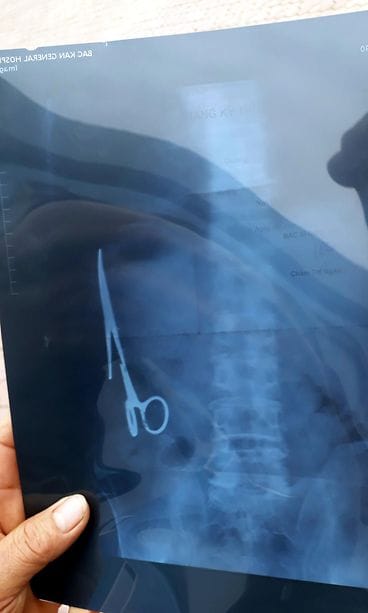

Vietnamilainen Ma Van Nhat, 54, meni taannoin käymään lääkärissä, koska vatsaan sattui. Kipristelyn syyksi paljastuivat hajamielisen kirurgin lähes kaksi vuosikymmentä sitten Nhatin vatsaan unohtamat leikkaussakset.

Nhat joutui leikkaukseen vuonna 1998 auto-onnettomuuden jälkeen.